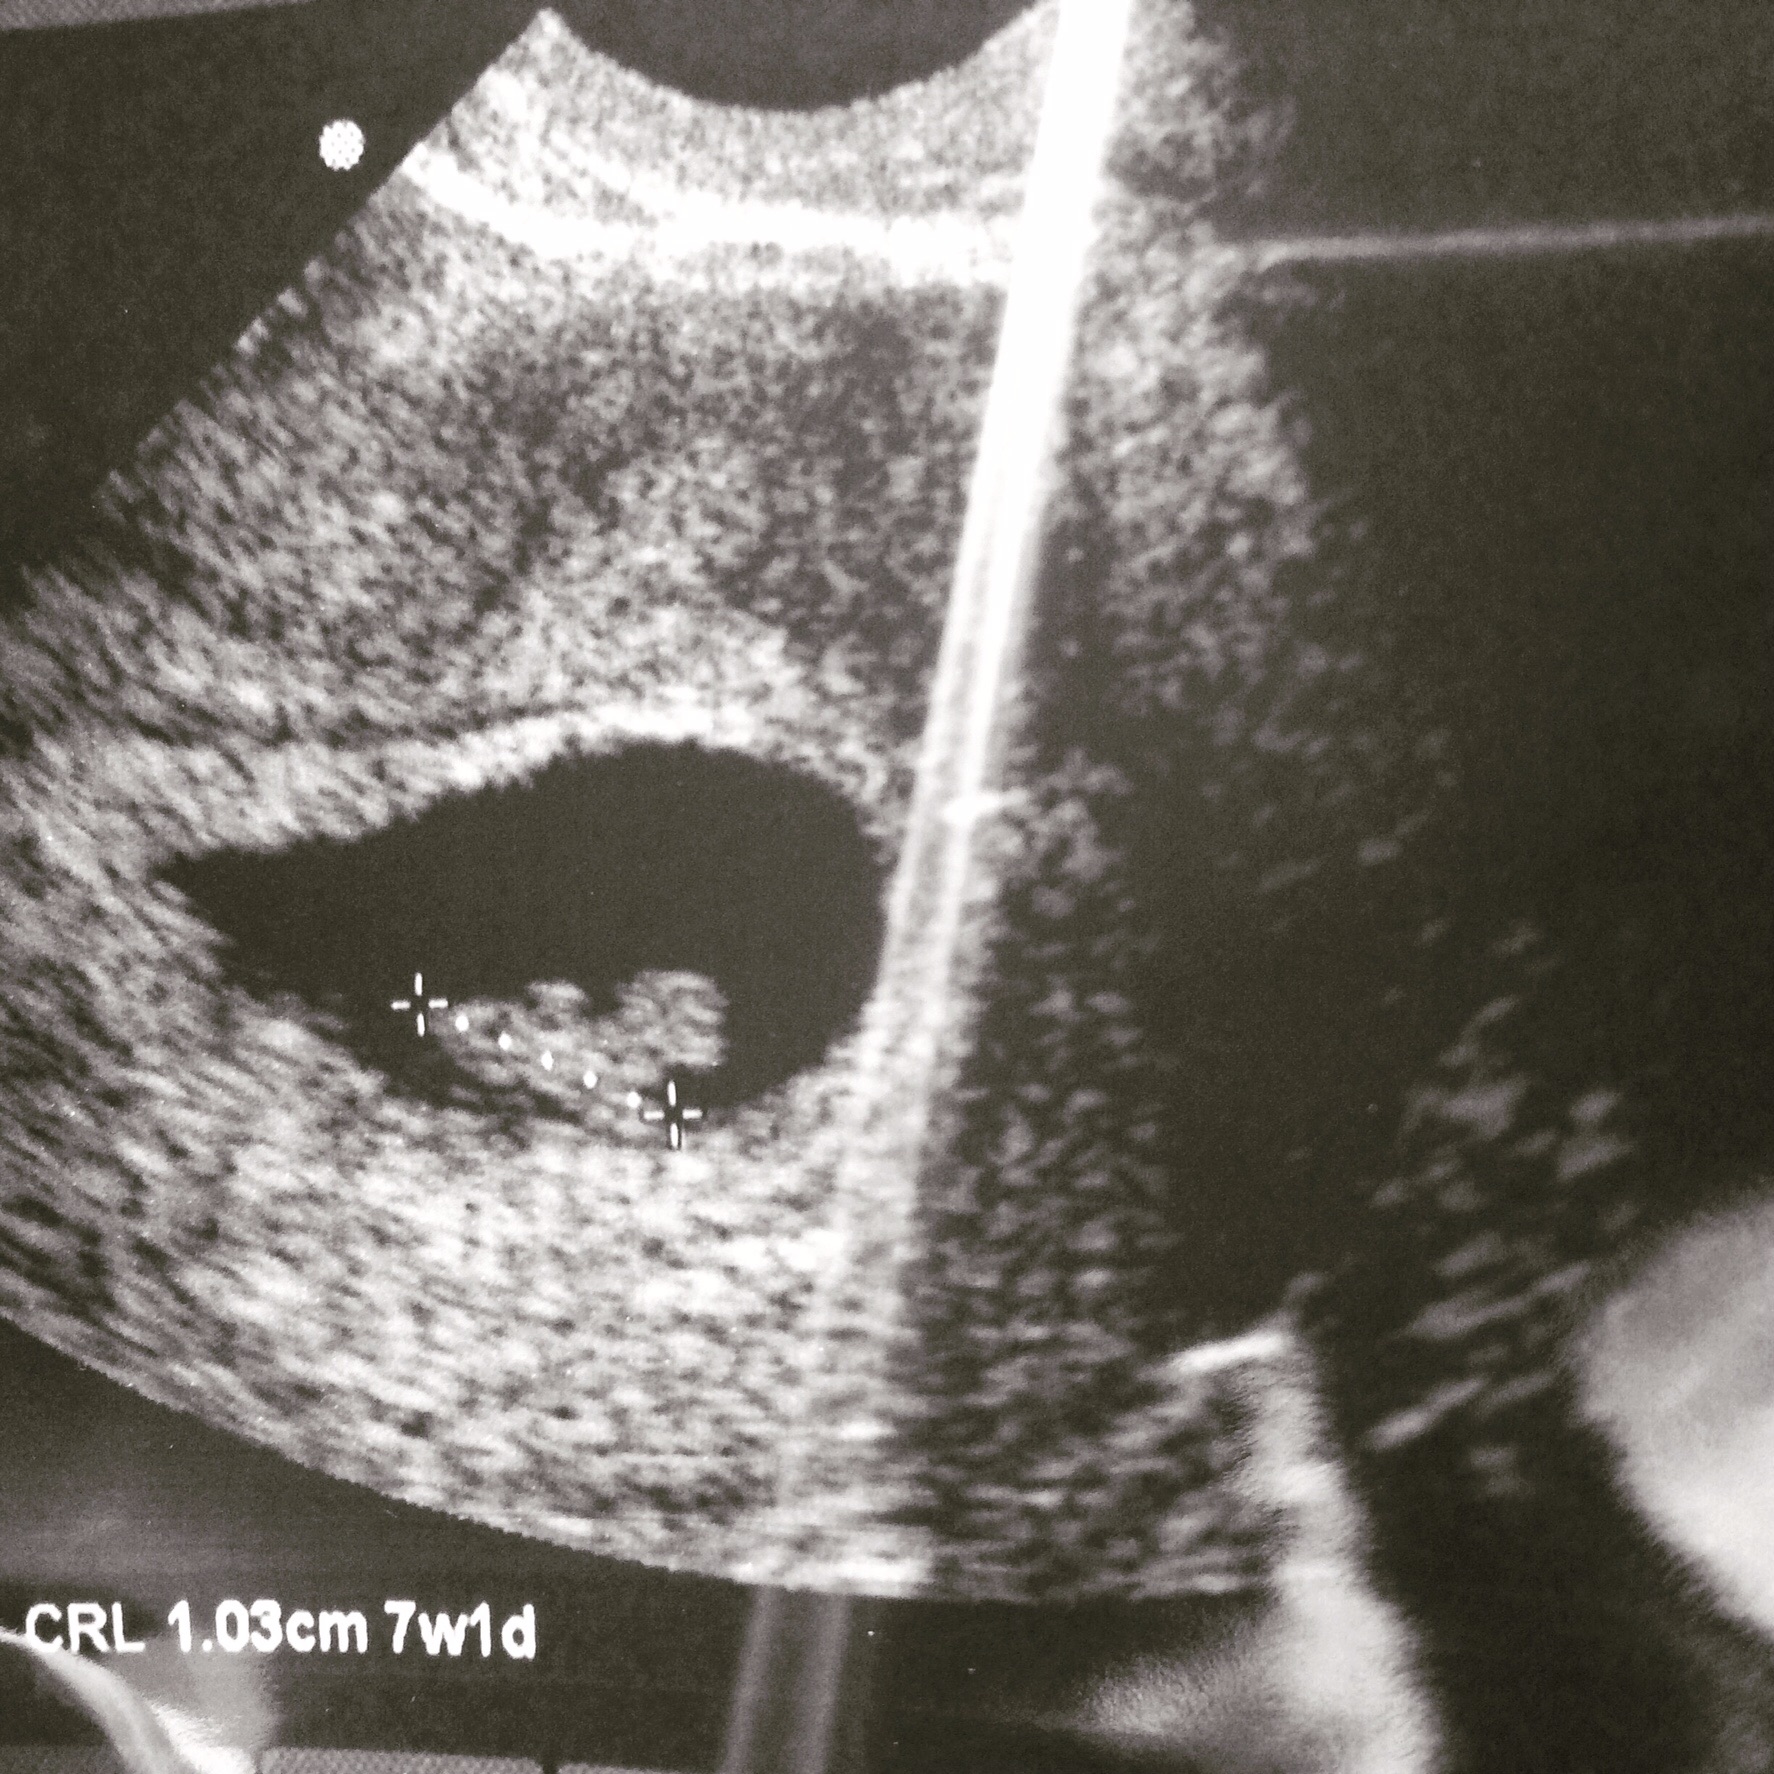

First time momma-to-be here! We are due March 15th, so I am 8 weeks 3 days today. I had my second ultrasound on Wednesday of this week and we got to HEAR the heartbeat - 170 BPM. Amazing! DH & I have had 2 MMC in the last 8 months so getting to see baby growing & being healthy is amazing.